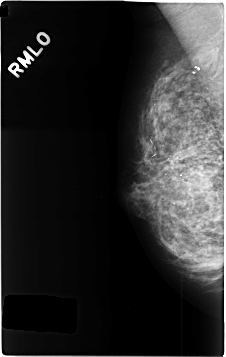

C_0344_1.RIGHT_MLO

RIGHT_MLO LINES 4632 PIXELS_PER_LINE 2928 BITS_PER_PIXEL 12 RESOLUTION 50 NON_OVERLAY